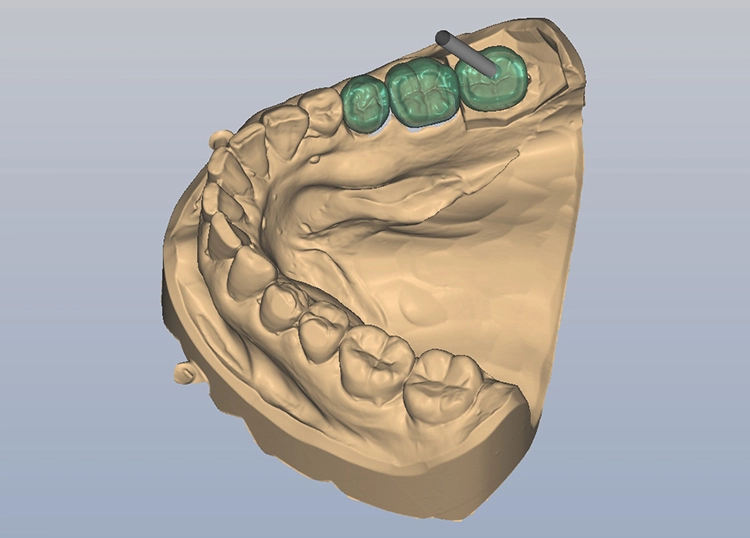

Bilder: Dr. Lampson / HannkerNach dem Ausgießen der Abformung sowie dem Scan des Gips- und Antagonistenmodells (Abb. 11a bis d) folgten das Kronendesign und die Fräsparametereinstellung per CAD/CAM-Programm (PowerMill Pro, Autodesk) (Abb. 12). Hergestellt wurden die Kronen aus Lithium-Disilikat-CAD/CAM-Blöcken (InitialTM LiSi Block, Farbe A2) (Abb. 13), die sich insbesondere durch eine hohe Opaleszenz bei hochtransluzenten (HT) Farbtönen auszeichnen und so auch ohne weitere Charakterisierung hochästhetische Ergebnisse erzielen.